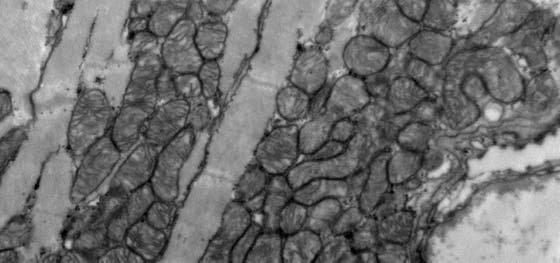

Mutaties in gen Tnnt2a veroorzaken ernstige cardiomyopathie

Onderzoekers uit de groep van Jeroen Bakkers ontdekten dat mutaties in het gen Tnnt2a een ernstige vorm van cardiomyopathie veroorzaken in zebravissen. De vissen ondergaan structurele veranderingen in het hart, meer stress en verstijving van de hartwand. Ook zijn ze onderhevig aan veranderingen in het hartritme, de samentrekkingen van het hart en de calciumgevoeligheid. Deze eigenschappen zijn ook terug te zien bij menselijke cardiomyopathieën, wat het model ideaal maakt voor onderzoek naar geneesmiddelen voor dit type ziekte. De resultaten werden op 20 april gepubliceerd in de speciale uitgave ‘Zebrafish Heart Development, Regeneration and Disease Modeling’ in het Journal of Cardiovascular Development and Disease.